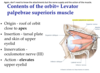

What does the levator palpebrae do and its innervation?

Function of superior rectus, lateral rectus, inferior rectus and medial rectus?

Function of superior oblique and inferior oblique muscles?

What are these nerves innervated by?

Remember that superior, inferior and medial rectus are involved in turning the eye in.